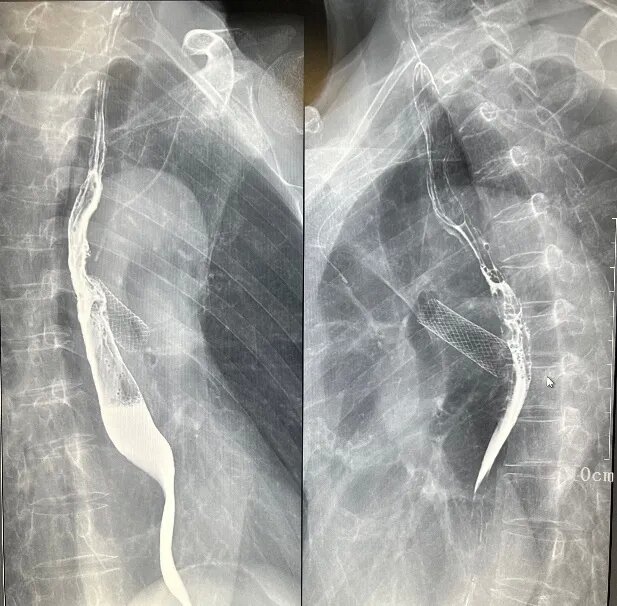

三、介入诊疗

如胆道造影、T管造影、ERCP,支持简单的介入治疗。